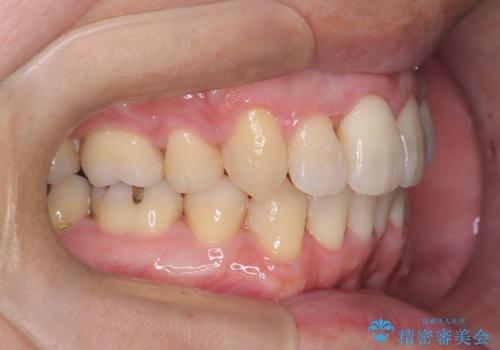

正面から見たときに右上2が全く見えないくらい、右上2が後ろに引っ込んでいる状態でしたが綺麗に並べる事が出来ました。

笑った時のスマイルラインもかなり綺麗になり大変ご満足いただく事が出来ました。

顔貌に対して歯の正中も合いました。